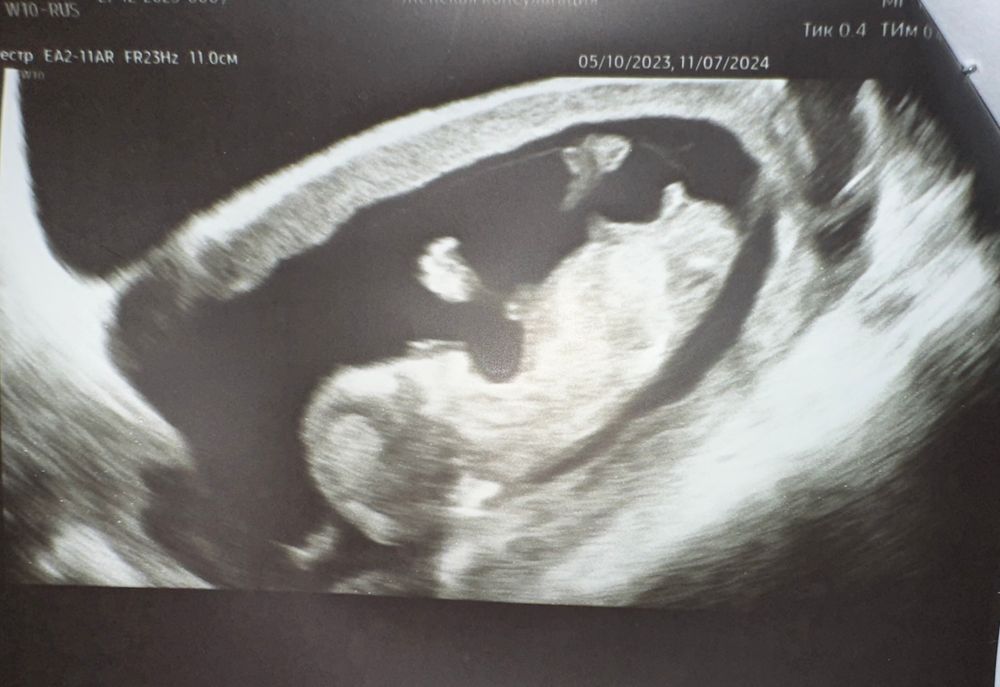

Lana Alaeva в Клуб беременных 2 года Пол на 12 недели Пол малыша Девочки, кто разбирается в этих бугорках? На кого больше похож малыш? Мне сказали приблизительно мальчик Посмотрите еще 20 записей на эту тему Отменить Ответить Та Что Любит ТЕБЯ Да, похож 27.12.2023 Ответить Кошка В Сапожках Мальчишка💙💙💙 27.12.2023 Ответить Кто то с форума Да, на мальчика похож))) 27.12.2023 Ответить На каком сроке узнали пол ребенка?) Есть ли разница в беременности мальчиком и девочкой? Чаты Беременных Выберите чат: Январята-2026 Февралята-2026 Мартята-2026 Апрелята-2026 Майчата-2026 Июнята-2026 Июлята-2026 Августята-2026